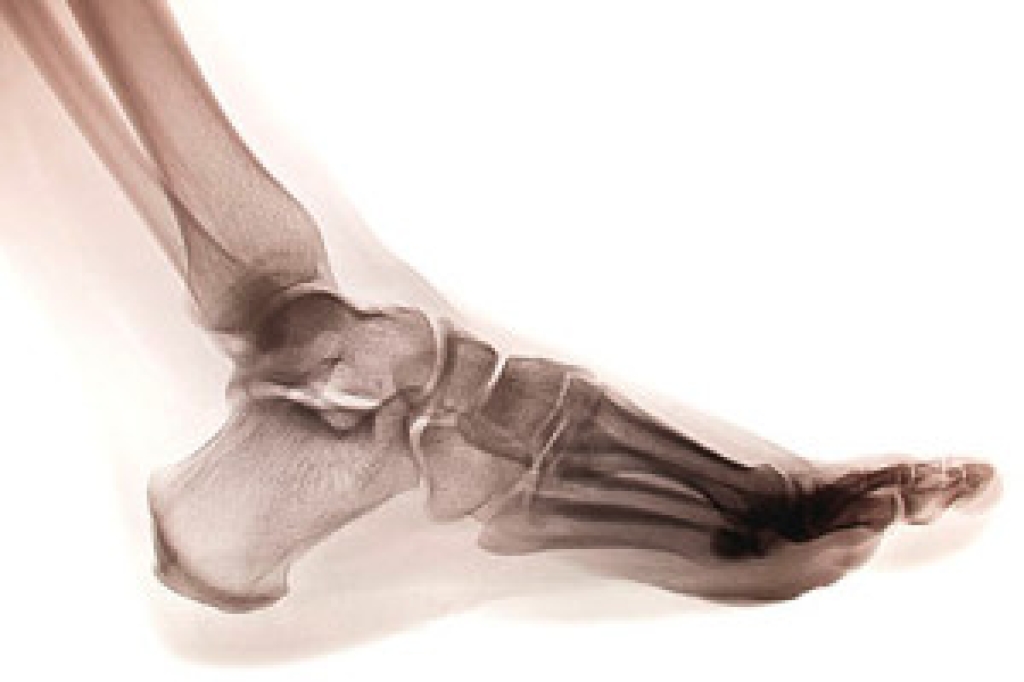

Flatfoot is a condition in which the arch of the foot is depressed and the sole of the foot is almost completely in contact with the ground. About 20-30% of the population generally has flat feet because their arches never formed during growth.

- Pain around the heel or arch area

- Swelling around the inside of the ankle

- Flat look to one or both feet

If you are experiencing pain and stress on the foot you may weaken the posterior tibial tendon, which runs around the inside of the ankle.